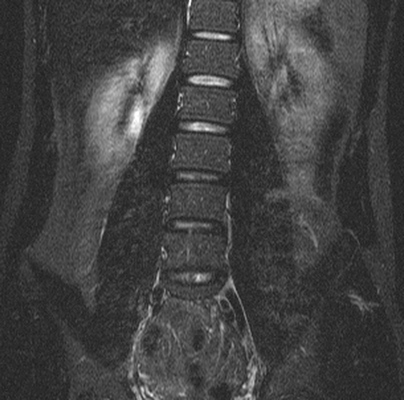

Правостороннее искривление позвоночника в коронарной плоскости при МР-сканировании

В каждом клиническом случае оптимальный вариант обследования определяет врач. Для диагностики деформаций позвоночного столба рентгена вполне достаточно, однако для более глубокого понимания проблемы могут потребоваться дополнительные сведения.

Магнитно-резонансная томография и рентгенография не заменяют друг друга. На обычных снимках с использованием Х-лучей нельзя выявить грыжи и патологии нервов. По результатам рентгенографии можно установить только косвенные признаки крупной и прогрессирующей опухоли. Магнитно-резонансная томография четко показывает подобные процессы, позволяет оценить степень их распространения и влияния на спинной мозг и на организм в целом.

Рентген важен для быстрого выявления искривления позвоночного столба. Результаты МРТ при сколиозе незаменимы для выбора тактики лечения пациента.